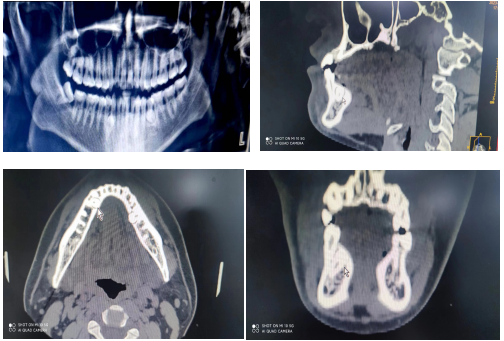

我院口腔科罗彬医生接诊一例双侧下颌前磨牙区舌侧埋伏阻生多生牙患者,术前通过临床检查及影像学资料对多生牙进行精准定位,判断多生牙形态、大小、阻生方向、牙根数量、与邻牙之间的关系及距离下牙槽神经管的距离。

术中通过舌侧翻瓣、去骨暴露多生牙,使用微创手机及车针于多生牙近远中向分离,去除冠部阻力,顺利拔除多生牙。(罗彬)